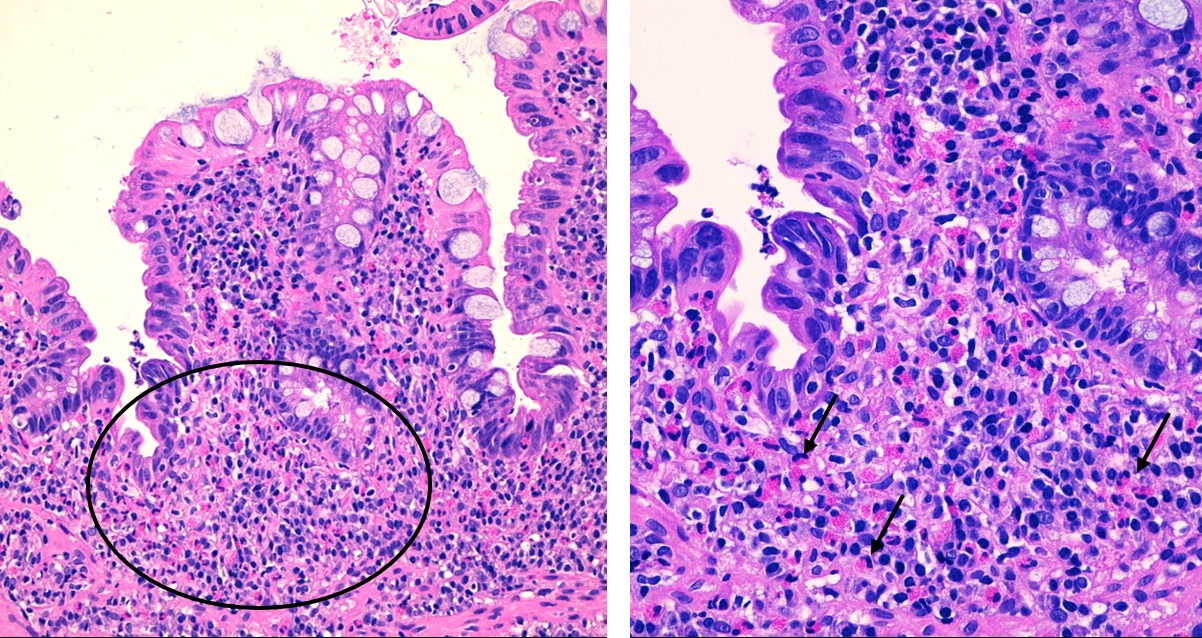

Niño de 13 años que ingresa por dolor abdominal en el hemiabdomen izquierdo y la fosa ilíaca derecha, intermitente, de dos semanas de evolución, asociando 1-2 deposiciones al día de consistencia líquida, con sangre roja al limpiarse en una ocasión, y vómitos y febrícula en los últimos tres días. No tiene tratamiento farmacológico habitual. Asma de esfuerzo. La familia describe otros tres episodios similares al descrito en los últimos 12 meses, de unas 3-4 semanas de duración, y por los que estaba siendo estudiado en otro centro. Durante el ingreso se realizan las siguientes pruebas complementarias: coprocultivo, parásitos en heces y toxina de C. difficile (negativos); calprotectina fecal: 90 mg/kg; bioquímica sanguínea (normal); hemograma (eosinofilia de 10 900/mm3); ecografía abdominal: engrosamiento de asas en fosa iliaca derecha e hipocondrio izquierdo (Fig. 1); gastroscopia sin hallazgos y colonoscopia con datos macroscópicos de ileítis terminal. Se recibe estudio anatomopatológico, que muestra una eosinofilia tisular intensa, más marcada en el íleon terminal y el ciego. En la ecografía de control a los tres meses persiste cierto engrosamiento de asas, con ligera mejoría respecto a imagen previa y analítica de control con normalización de la cifra de eosinófilos. El noveno mes de seguimiento el paciente presenta un episodio de febrícula, dolor abdominal intenso en fosa ilíaca derecha y vómitos, que es manejado con prednisona oral a 1 mg/kg. Evolución clínica posterior favorable.

| Figura 1. Ecografía abdominal. Se señala un asa intestinal de íleon terminal con un notable engrosamiento mucoso |